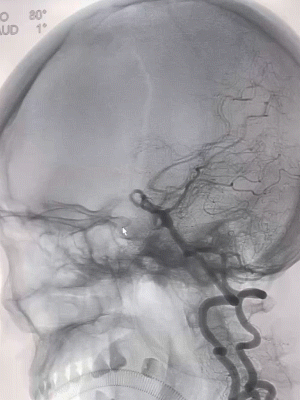

术后即刻影像(正侧位):造影显示动脉瘤瘤内造影剂滞留,载瘤动脉、双侧大脑后动脉,小脑上动脉显影良好,逐次撤除支架微导管,中间导管,6F长鞘。

后循环动脉瘤传统治疗方式(弹簧圈+支架)的并发症发生率高且治愈率低。目前研究发现FD治疗夹层动脉瘤的完全闭塞率最高且并发症率最低,本例患者采用国产Tubridge®血流导向密网支架,在治疗椎基底动脉夹层动脉瘤时,预后良好,围手术期并发症少。